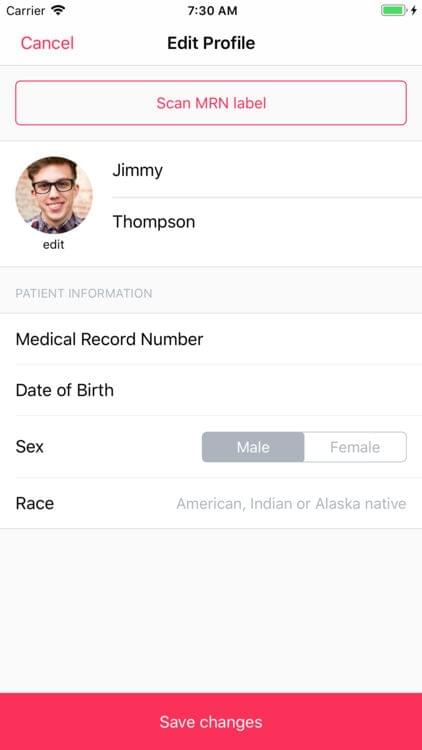

Skin — Patient Profiles

Skin is a digital health imaging app for tracking of moles and skin lesions. The platform is targeted towards academic researchers, physicians and patients looking to integrate a robust sharing platform for the management and surveillance of dermatological conditions. This app gives medical institutions and physicians a secure option to create scalable studies with hundreds of patient participants. The tool is intended to help support the creation of an intelligent model for the accurate diagnosis of skin diseases.